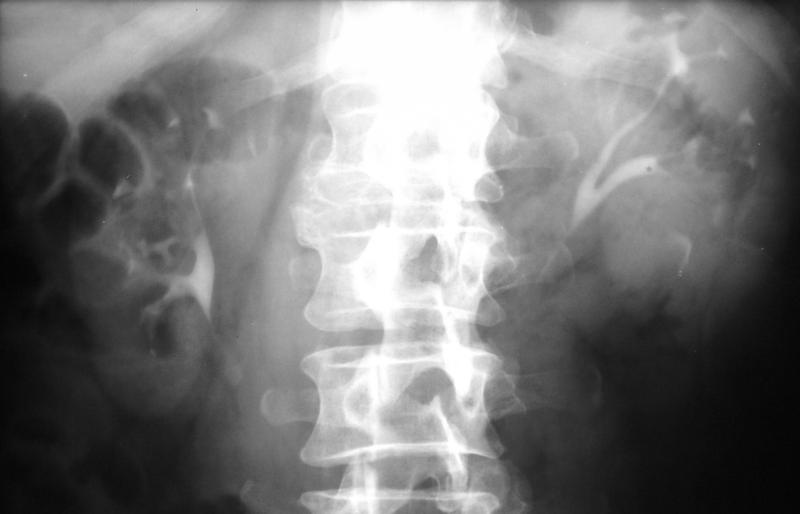

IVU:

Pyelonephritis chronica